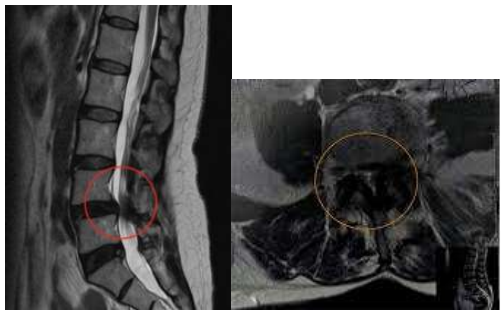

Paciente de 68 anos, sexo masculino, veio encaminhado do município de São Bento do Una-PE para parecer com

a neurocirurgia. Tinha relato de lombalgia, claudicação, dor, dormência e fraqueza em membros inferiores

progressivas, além de incontinência urinária há 6 meses. Negou diabetes, hipertensão e dislipidemia. É vendedor

ambulante de leite, faz uso de bicicleta no trabalho e relatou queda da mesma 3 dias antes do surgimento dos

sintomas, sem perda de consciência e sem vômitos. Ao exame físico: pulsos femoral, poplíteo, pedioso e tibial

posterior presentes bilateralmente, sem alterações de pele em membros inferiores, sinal de Lasègue negativo

bilateralmente, teste de Kemp com dor e formigamento durante sua execução em membros inferiores, além de

alterações motoras e sensitivas correspondentes às raízes nervosas de L4, L5 e S1.

Foi internado em enfermaria da Neurocirurgia, fez tomografia computadorizada (TC) de crânio que foi normal

para a idade, TC e ressonância magnética (RM) de toda coluna que mostrou estenose importante de canal

vertebral na altura de L4, algumas alterações degenerativas discretas no restante da coluna, incluindo a cervical

e sem sinais de fratura vertebral.